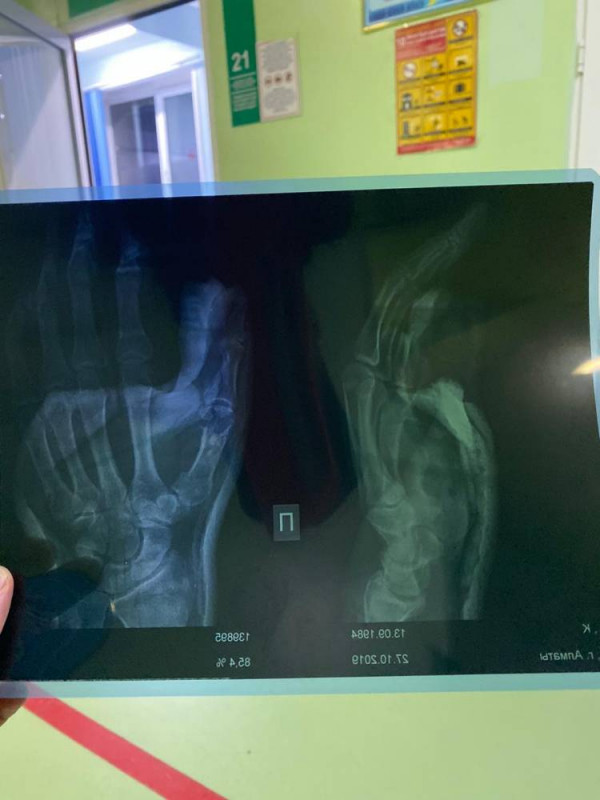

Казахстанский боксер Канат Ислам, который накануне одержал победу над намибийцем Уолтером Каутондоквой, провел четыре раунда из десяти со сломанной рукой, передает Tengrinews.kz со ссылкой на Vesti.kz.

Как сообщили в команде боксера, начиная с седьмого раунда, Ислам бился со сломанной кистью правой руки. Из-за этого он не мог наносить удары по сопернику. После поединка казахстанскому боксеру наложили гипс на травмированную руку.